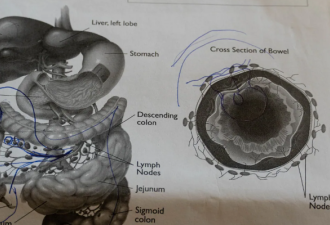

第三:那些手术的图片是以前的新闻,是一个男的生吃鳝鱼,钻到内脏里的手术图。

医生科普:塞入肛门的泥鳅和黄鳝之类活物,会垂死挣扎,钻破肠道。临床上见到,多是钻破乙状结肠,如不及时手术,病人必死无疑。而动手术,由于腹腔被大便所污染,也必须分两步做。首先做结肠造瘘,乙状结肠修补,待病情允许,几个月后再接回肠子。病人即使能捡回一条命,也是痛不欲生,会留下不少后遗症。

X光照片中黄鳝大逃亡,显然是在疯狂找出口。